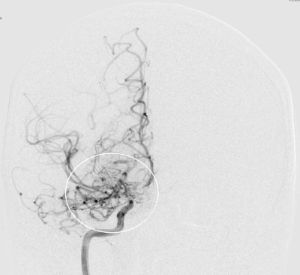

Angiografie einer Moymoya

Auf dem Bild mit einer Gefäßdarstellung “Angiographie” kann man die dünnen Kollateralen (Wolken-ähnliches Bild) um die Gefäßengstelle am Ende der inneren Halsschlagader erkennen.

Moyamoya wurde 1957 erstmals von den Japanern Takeuchi und Shimizu beschrieben. Die Erkrankung kommt vor allem im asiatischen Raum (insbesondere Japan und Korea) häufiger vor, wobei man von einem Auftreten (Inzidenz) von ca. 0.35/100.000 Einwohnern/Jahr ausgegangen wird. Für den europäischen Raum gibt es bis heute keine verlässlichen Daten, jedoch schätzt man, dass die Erkrankung hier ca. 10x seltener als oben genannt vorkommt. Der Name „Moyamoya“ stammt aus dem Japanischen und bedeutet übersetzt „Rauchwolke“, was auf das diffuse Erscheinungsbild feiner Kollateralgefäße in der Gefäßdarstellung „Angiographie“ zurückzuführen ist.